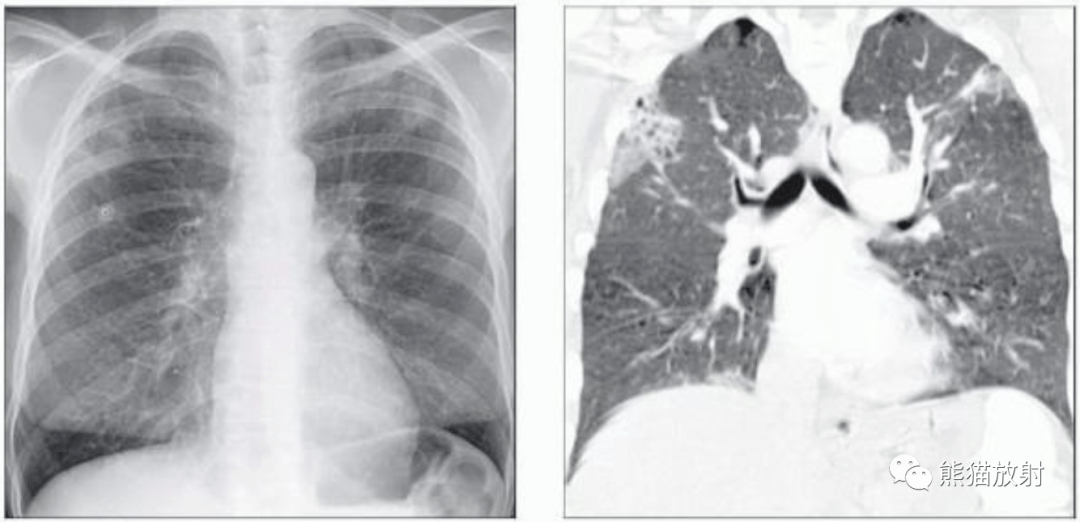

病案肺吸虫感染似肺癌复发

图片尺寸396x418

肺孢子菌肺炎卡肺肺寄生虫病丨影像表现

图片尺寸1021x496